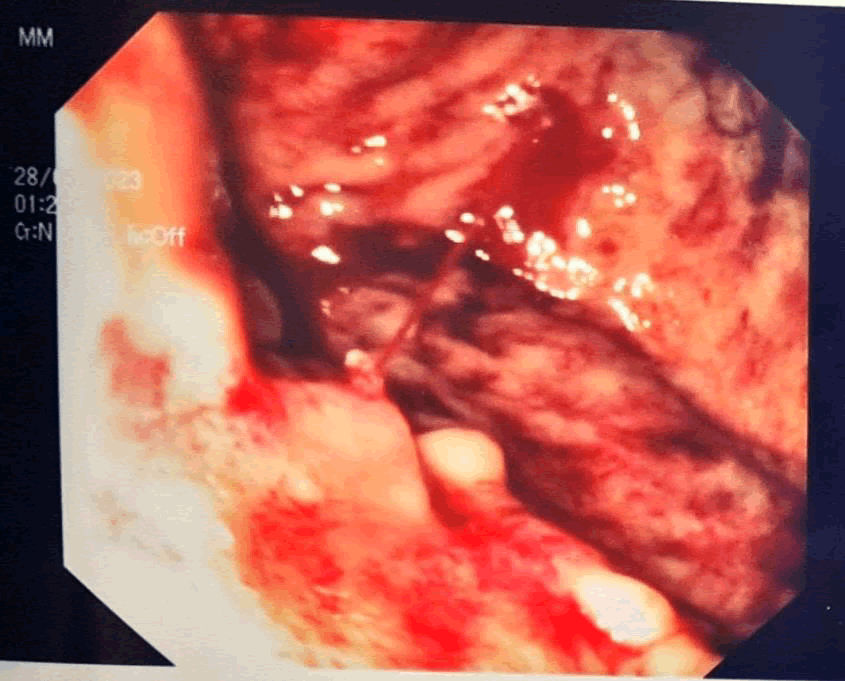

A 30+0 weeks of gestational age male newborn was delivered after 2 minutes, with Apgar score of 1-5-7 at 1-5-10 minutes. In the meantime, EGD was performed. After multiple washings and aspiration of the gastric hematic content, despite changes of the patient’s position, the bleeding site was not identified. A CT-angiography was then performed; however, no active bleeding was evidenced. Straight afterwards, a second EGD was performed and, after removal of blood clots, a bleeding DL was eventually identified on the anterior wall of gastric fundus (Figure 2). Epinephrine was injected, and over-the-scope endoclip was placed obtaining hemostasis (Figure 3).

XXXXXX

Figure 2. GI endoscopy showing active bleeding from DL.